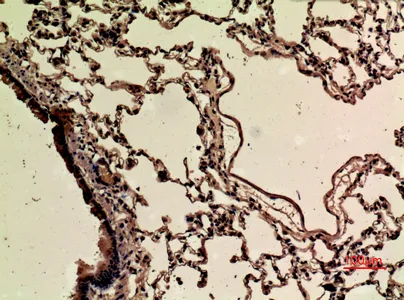

CD68 Rabbit Polyclonal Antibody

Cat: APRab08436

Size1:50μl Price1:$118

Size2:100μl Price2:$220

Size3:500μl Price3:$980

Size2:100μl Price2:$220

Size3:500μl Price3:$980